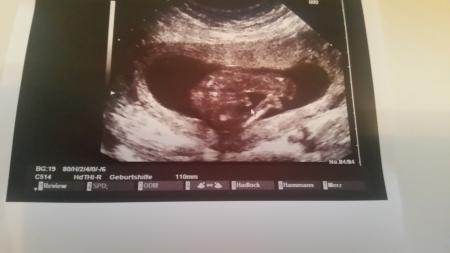

Was meint ihr? Junge oder Mädchen?

Bild zu Junge oder Mädchen? - Schwanger - wer noch? Rund um die Schwangerschaft

Mädchen

Hallo, Ich würde Junge sagen!

Mädchen. Was sagt der Arzt? Welche Woche überhaupt?

Für mich ist es eindeutig ein Mädchen!! Sah bei allen 3en Bauchmäusen so aus und war dann auch immer so.